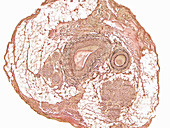

13296404 - Thickened muscular artery, light micrograph

12634785 - Carotid artery, LM

12960253 - Blood vessels,light micrograph